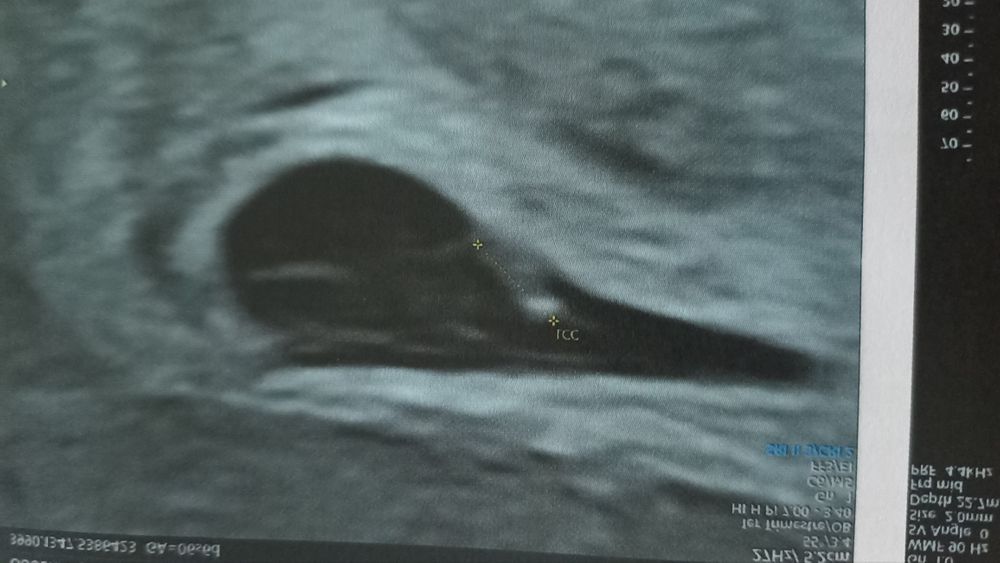

На данном узи можно будет видеть что белый участок рассеивается в правую сторону. Это говорит что крепление плаценты с правой стороны.

ЕСЛИ ХОРИОНА СИЛЬНО БОЛЬШЕ ПО ПРАВОЙ СТОРОНЕ - то это говорит о ДЕВОЧКЕ!

ЕСЛИ ХОРИОНА СИЛЬНО БОЛЬШЕ ПО ЛЕВОЙ СТОРОНЕ - то это говорит о МАЛЬЧИКЕ!